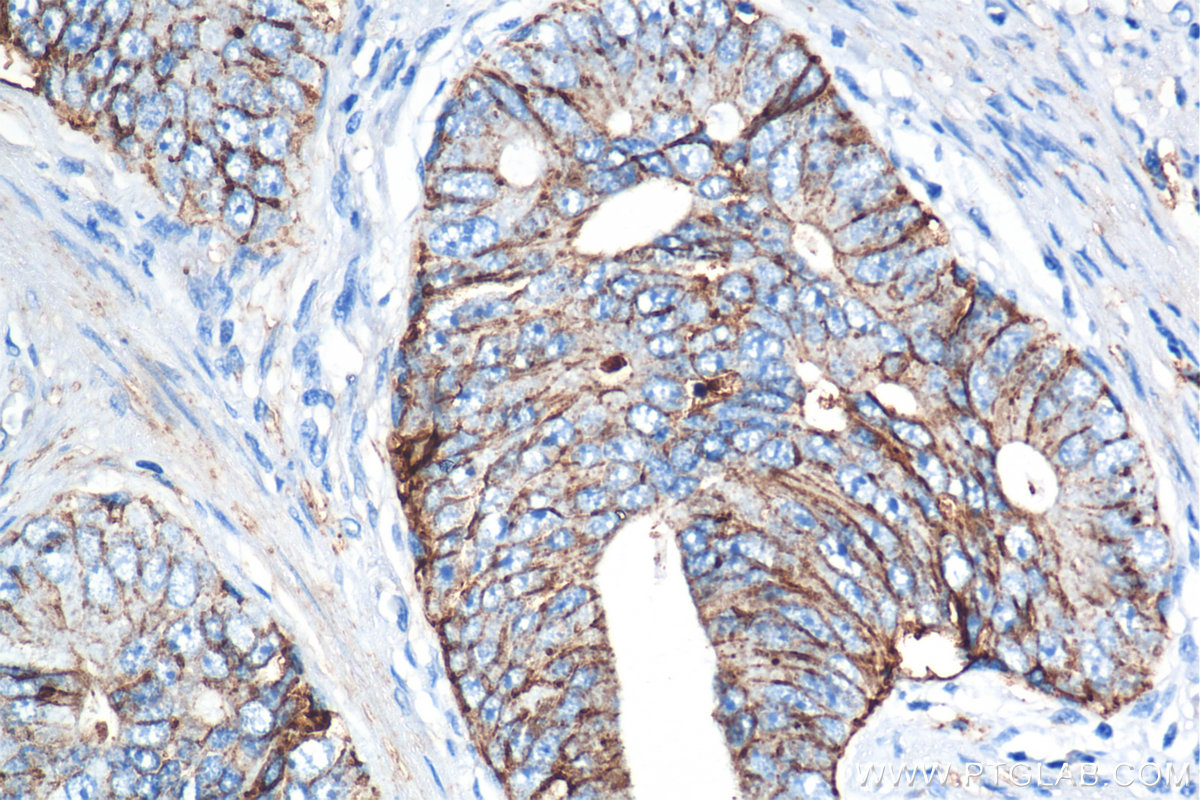

| Positive IHC detected in | mouse spleen tissue, human prostate cancer tissue, mouse kidney tissue, rat spleen tissue Note: suggested antigen retrieval with TE buffer pH 9.0; (*) Alternatively, antigen retrieval may be performed with citrate buffer pH 6.0 |

| Immunohistochemistry (IHC) | IHC : 1:1000-1:4000 |